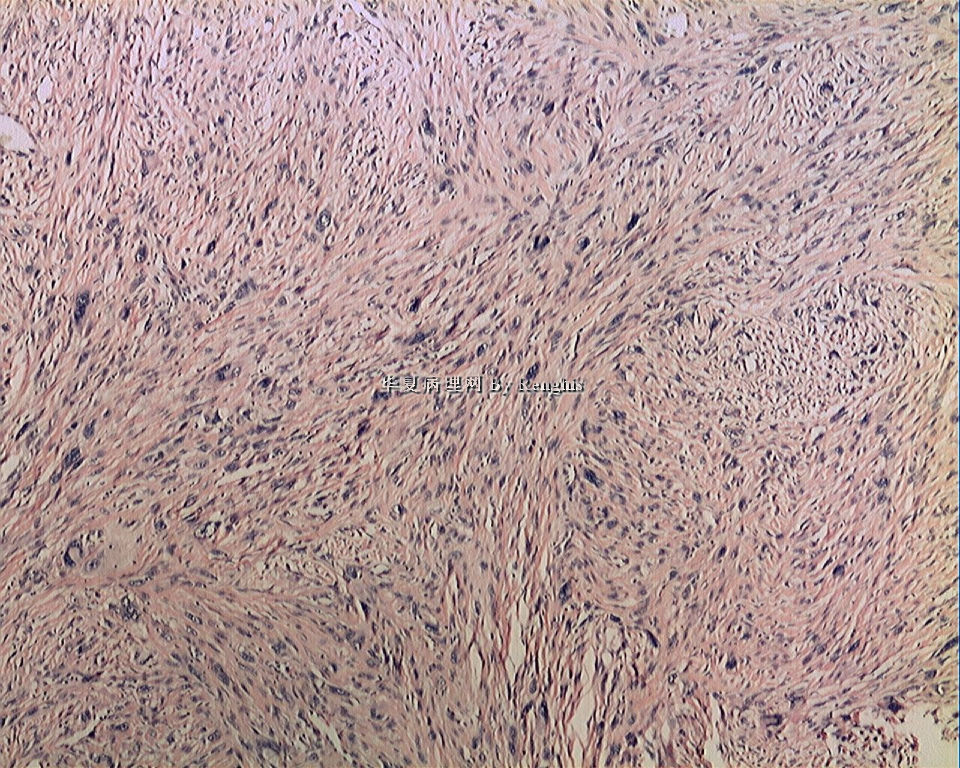

女,29岁,左大腿内侧肿物直径2.8cm,切面灰白、实性、质中,似有包膜。

本人认同此例是一例比较典型的纤维肉瘤,瘤细胞程束状、鱼骨状及编织状排列,部分瘤细胞异型性明显,免疫组化vimentin阳性,SMA灶状弱阳性,desmin阴性,S100阴性,CK阴性,EMA阴性,余记不得了,明天看看再上传。